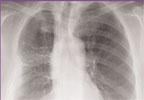

July 23, 2010 -- BrachyMESH is a prefabricated sterile polyglactin 910 mesh, embedded with I-125 sources (Model 6720) to physician specifications. It was shown by Oncura at the 2010 annual AAPM (American Association of Physicists in Medicine) meeting in Philadelphia.

It is designed to eliminate technical barriers, reduce operating room time, reduce staff radiation exposure and allow for a wider range of patients to benefit from lung brachytherapy and the permanent interstitial implantation of selected tumors which are localized, either unresectable or resectable after excision of the primary lesion, and of low to moderate radiosensitivity.